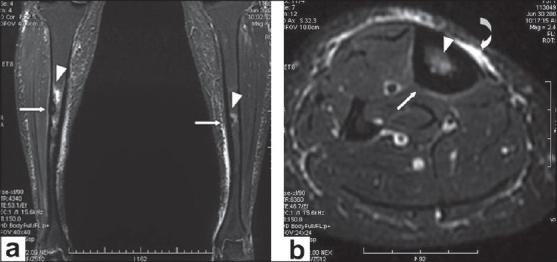

Ribbing disease is a rare sclerosing dysplasia that involves long tubular bones, especially the tibia and femur. It occurs after puberty and is reported to be more common in women. In this article we describe how Ribbing disease can be differentiated from diseases like Engelmann-Camurati disease, van Buchem disease, Erdheim-Chester disease, osteoid osteoma, chronic osteomyelitis, stress fracture, etc.

里宾病是一种罕见的骨硬化发育异常疾病,累及长管状骨,尤其是胫骨和股骨。它在青春期后发病,据报道在女性中更为常见。在本文中,我们描述了如何将里宾病与恩格尔曼-卡穆拉蒂病、范布赫姆病、厄尔德海姆-切斯特病、骨样骨瘤、慢性骨髓炎、应力性骨折等疾病相鉴别。